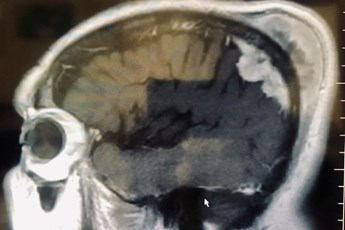

Baş ağrısı, baş dönmesi ve denge kaybı hissi şikayetleriyle Afyon PARKHAYAT Hastanesi Beyin ve Sinir Cerrahi doktorlarından Op.Dr. Celal Özbek Çakır’a başvuran 75 yaşındaki hasta yapılan detaylı muayene tahlil ve tetkikler sonrası MR'ında görülen serebral korteksten başlayıp durayı ve kemiği erode ederek cilt altına kadar uzanan kitle tespit edildi. Akabinde 4 saat süren başarılı operasyonla tümör tamamen çıkarıldı ve hasta sağlıklı bir şekilde taburcu edildi.